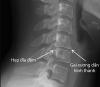

Gai cột sống là loại bệnh thoái hóa cột sống mà trong đó xuất hiện các phần xương mọc ra phía ngoài và hai bên của cột sống gọi là gai xương

Gai cột sống có thể xuất hiện ở nhiều vị trí trên xương sống của cơ thể nhưng thông thường hay gặp gai cột sống cổ và gai cột sống lưng